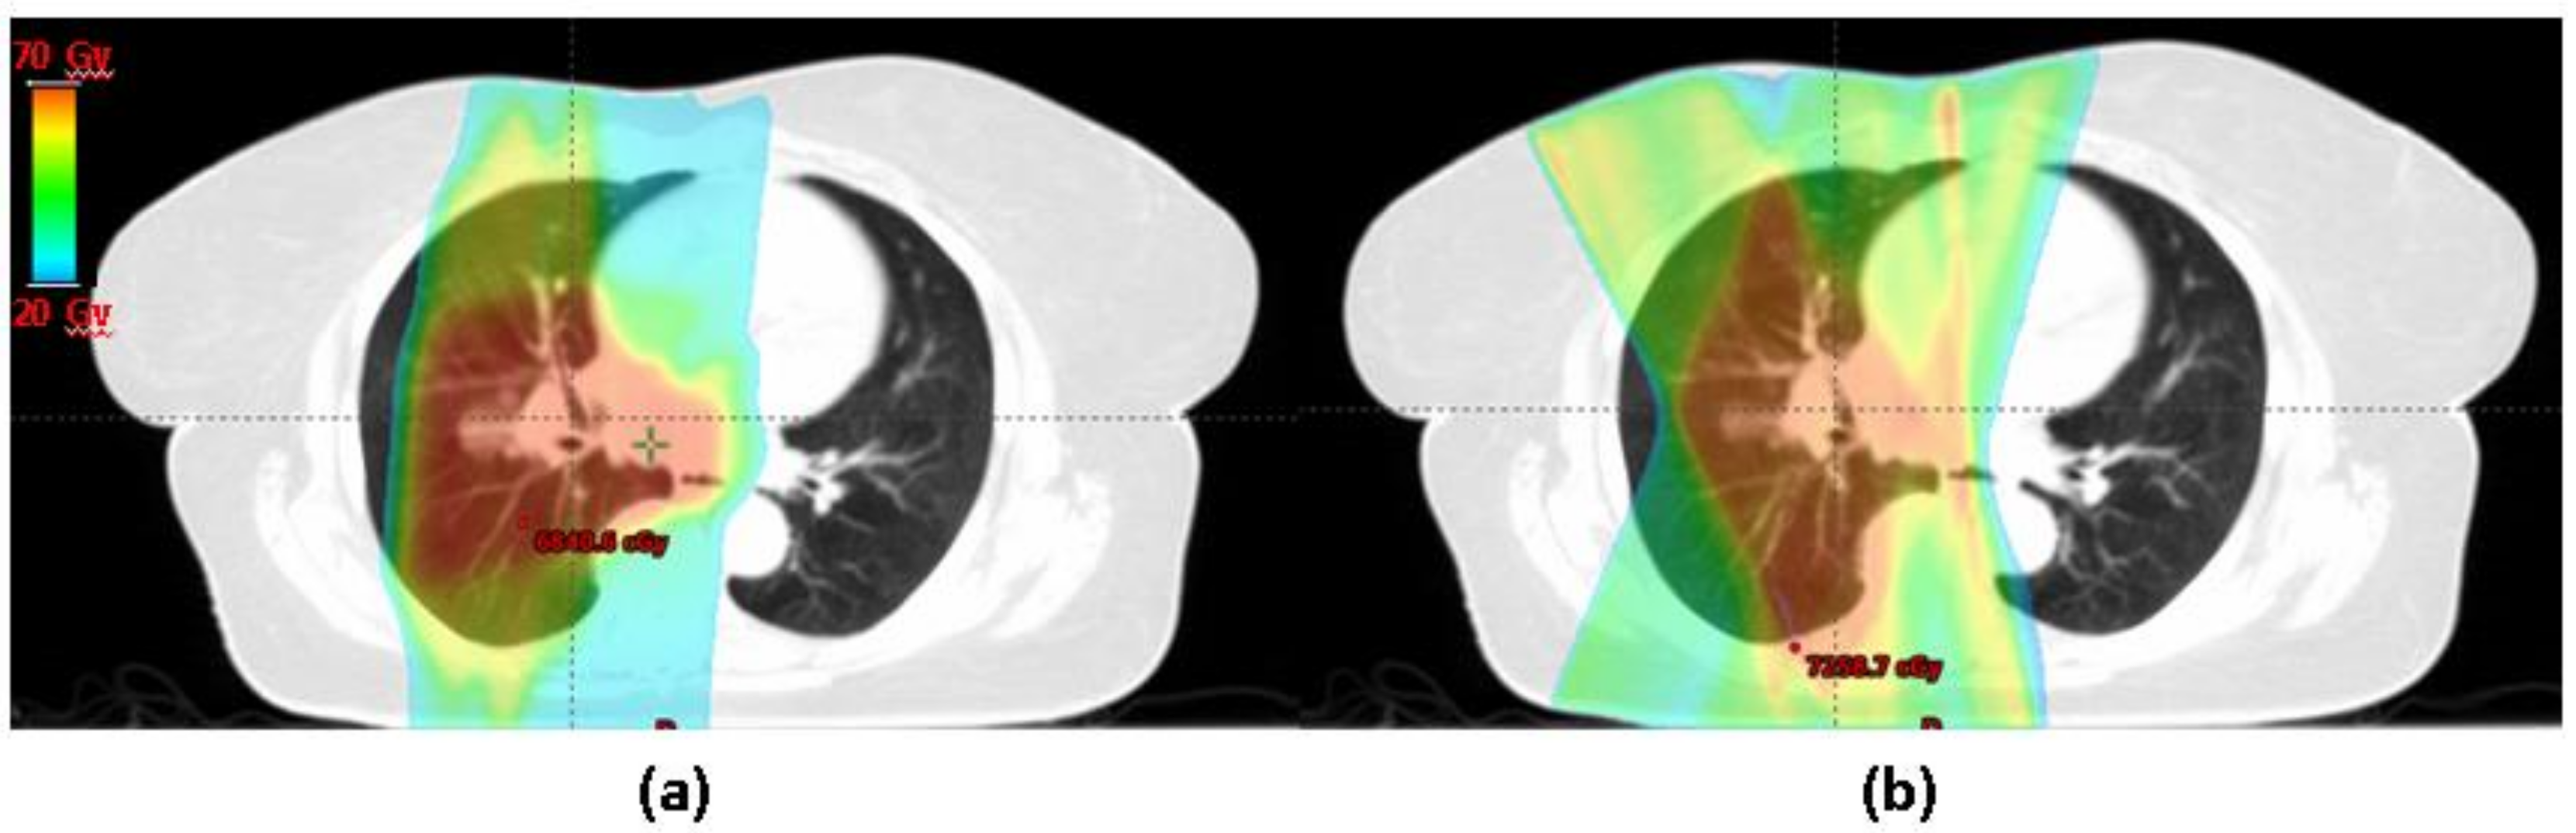

- Berman, A.T.; Teo, B.-K.K.; Dolney, D.; Swisher-McClure, S.; Shahnazi, K.; Both, S.; Rengan, R. An in-silico comparison of proton beam and IMRT for postoperative radiotherapy in completely resected stage IIIA non-small cell lung cancer. Radiat. Oncol. 2013, 8, 144. [Google Scholar] [CrossRef] [PubMed]

- Zhang, X.; Li, Y.; Pan, X.; Xiaoqiang, L.; Mohan, R.; Komaki, R.; Cox, J.D.; Chang, J.Y. Intensity-modulated proton therapy reduces the dose to normal tissue compared with intensity-modulated radiation therapy or passive scattering proton therapy and enables individualized radical radiotherapy for extensive stage IIIB non-small-cell lung canc. Int. J. Radiat. Oncol. Biol. Phys. 2010, 77, 357–366. [Google Scholar] [CrossRef] [PubMed]